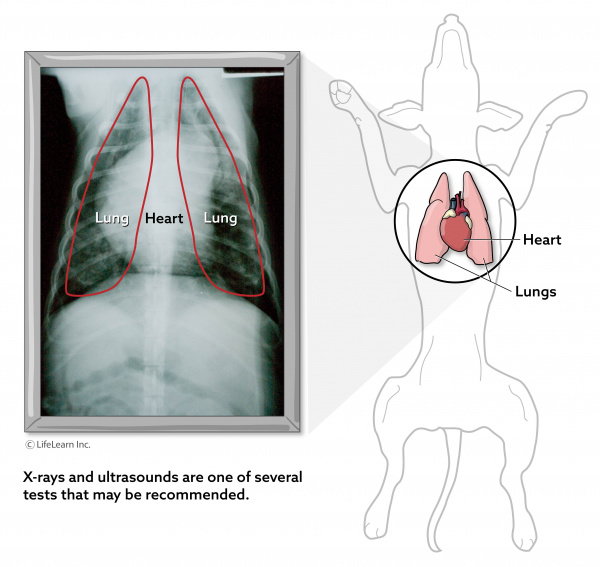

The most important test in diagnosing ARDS is a blood test, called a blood gas analysis, which provides detailed information on the levels of oxygen and carbon dioxide in the blood. Your veterinarian will also likely perform a complete blood cell count, serum biochemistry profile, and urinalysis to assess your dog’s overall health. Chest X-rays and an echocardiogram (ultrasound of the heart) may also be performed.

In addition to these tests, your veterinarian will perform tests to determine the underlying cause of your dog’s illness (if it has not already been identified). These tests may include X-rays of the abdomen, ultrasound, exploratory surgery, bacterial cultures, and other diagnostic tests that vary based on the exam findings.